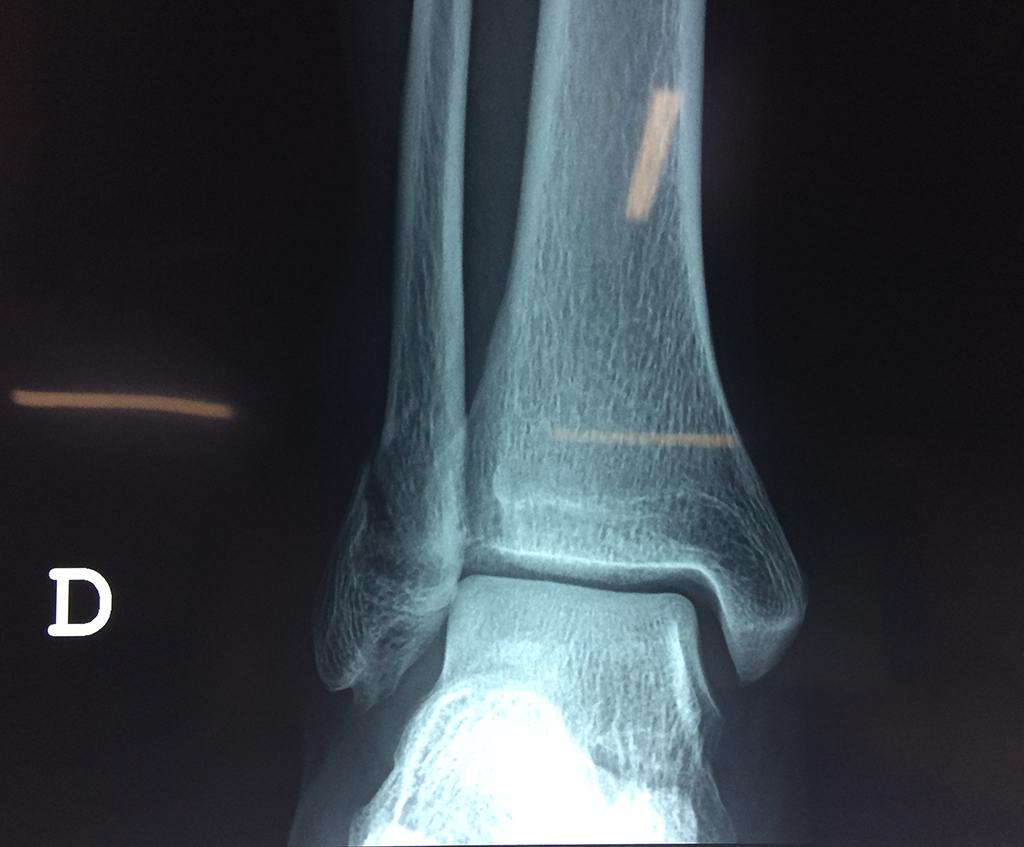

Cirugía de Tibia y Peroné

Algunas fracturas de tobillo pueden requerir cirugía si:

- Los extremos de los huesos están desalineados entre sí (desplazados).

- La fractura se extiende hasta la articulación del tobillo (fractura intra-articular).

Cuando se necesita cirugía, es probable que esta implique el uso de clavijas de metal, tornillos o placas para sostener los huesos en su lugar mientras la fractura se consolida. Los elementos de soporte pueden ser temporales o permanentes.